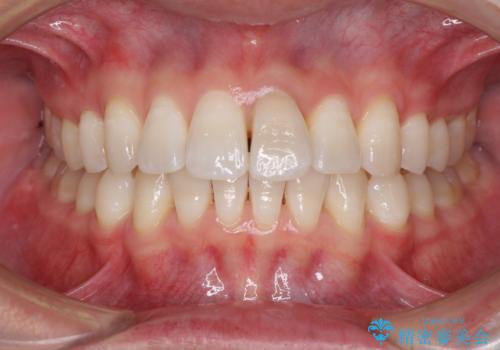

前歯のデコボコを治したい インビザラインによる矯正治療

- 前歯のデコボコを治したいとのことで来院された患者様です。

上下顎ともに歯列全体の後方移動とIPR(歯と歯の間を削る)によってデコボコが解消するように設計し、インビザラインにより治療を行うこととしました。

矯正治療後、前歯の形と色が気になるとのことでしたが、大分前に失活している(神経が取り除かれている)歯であり、その影響で変色しているため、オールセラミッククラウンによる補綴治療をおすすめいたしました。